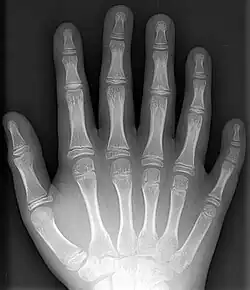

- Polydactyly – additional fingers or toes[4]

- Supernumerary bones – these additional bones are fairly common, particularly in the feet, and are frequently mistaken for fractures on x-rays.

- Syndactyly – webbing between the fingers or toes[4]